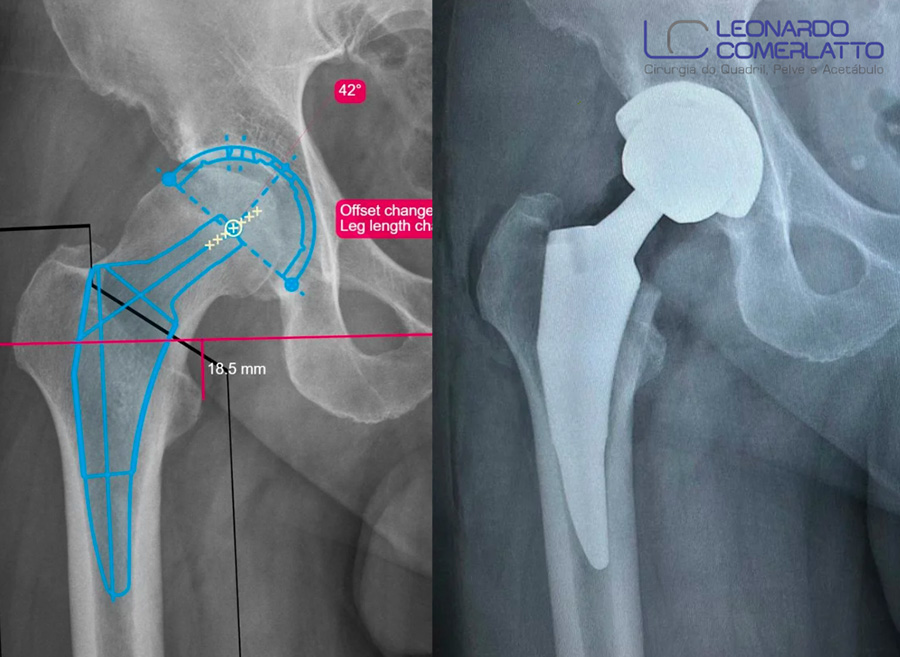

O sucesso dessa cirurgia está relacionado com uma indicação precisa, um planejamento pré-operatório rigoroso e com a utilização de uma prótese com resultados conhecidos e confiáveis. Além disso, a realização da cirurgia por uma equipe experiente, capacitada e em constante treinamento impacta de forma definitiva na capacidade de executar o procedimento próximo à perfeição.